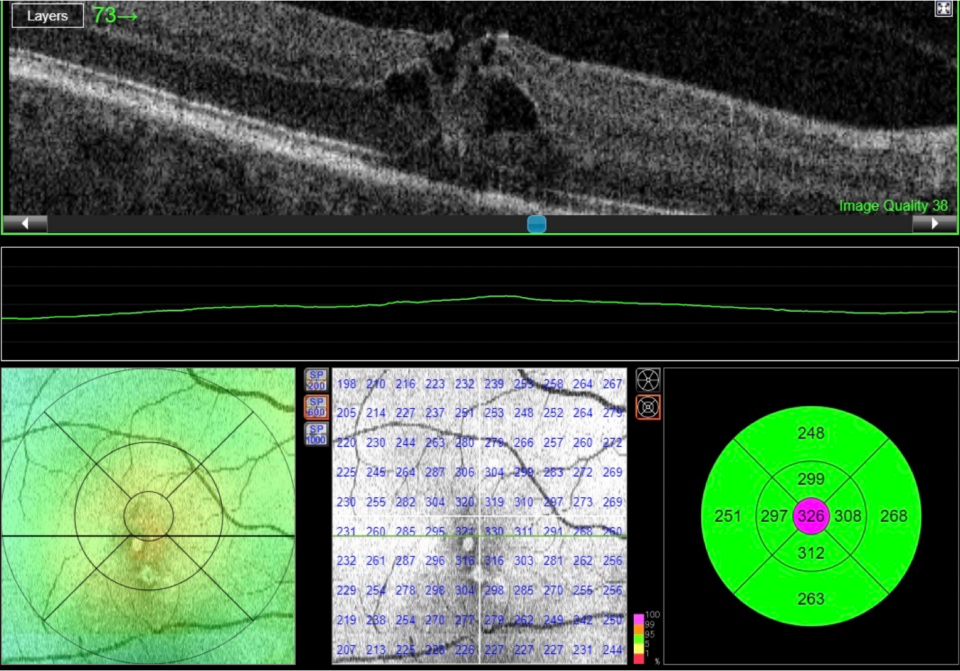

Case: Macular Pathology

A 67-year-old male attends your clinic with reduced vision OD.  He finds contours difficult to see and letters can also be difficult to distinguish.

The vision has worsened in the last half year and especially in the last month. It's uncertain whether he experiences any metamorphopsias.

BCVA half a year ago was 1.2 (6/5). Today it is 0.3 (6/20) (PH 0.3 [6/20]).

Anterior segment is without any indication of his reduced vision. Posterior segment has normal vasculature, optic nerve head and retina.